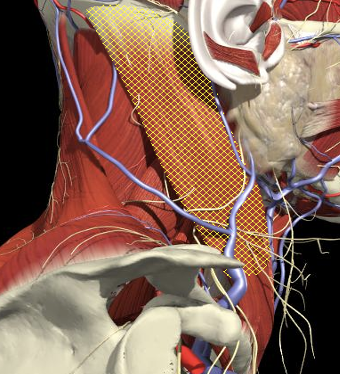

Structures to Avoid

Brachial Plexus

- From the intervertebral foramina, the 5 roots of the brachial plexus exit above the transverse processes of the corresponding cervical vertebrae and traverse through the interscalene groove before entering the floor of the posterior triangle of the neck.

- The upper, middle and lower trunks are enclosed within the interscalene fascial sheath as they emerge between the scalene muscles.

The Interscalene Groove

- The interscalene groove lies immediately behind the lateral border of the clavicular head of the sternocleidomastoid muscle at the level of the cricoid cartilage (C6)

- Approximately 1cm above the separation of the sternal and clavicular heads of the sternocleidomastoid muscle.

The BP lies inferior to a line from the posterior margin of the sternomastoid at the level of the cricoid cartilage to the midpoint of the clavicle

The BP lies inferior to a line from the posterior margin of the sternomastoid at the level of the cricoid cartilage to the midpoint of the clavicle. Scalenus medius is behind and above line.

Interscalene Groove & Brachial Plexus

Interscalene groove

Nerves in Posterior Triangle

Accessory nerve

-

Lies on LS, enters 1cm cranial to EP posterior border of SCM and runs on line to between middle and lower third of trapezius.

Should inject splenius and levator over 1cm above EP

Cervical plexus cutaneous branches

Mid point of posterior border